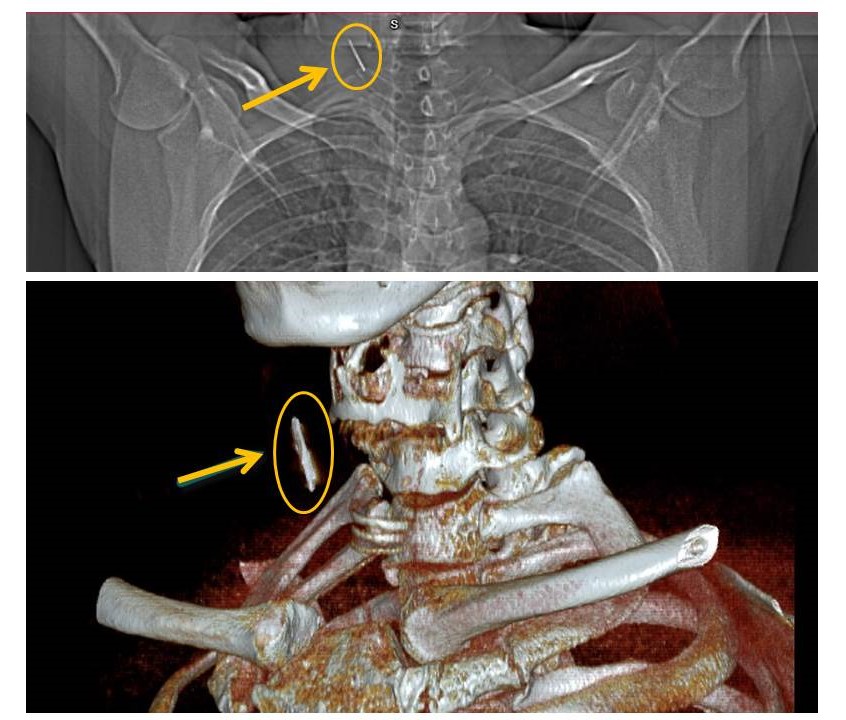

Chỉ khi vô tình đến Bệnh viện Phú Thọ để khám sức khỏe, khi chụp phim Xquang, các bác sĩ phát hiện có dị vật cản quang cắm sâu ở vùng cổ bên phải người bệnh.

Sau khi được kiểm tra lại bằng các kỹ thuật hình ảnh chuyên sâu xác định dị vật có tính cản quang mạnh các bác sĩ nghĩ đến có mảnh kim khí ở cổ bệnh nhân, Vị trí dị vật ngang mức đốt sống cổ 6 – 7, gần với mạch cảnh.

Chiếc đinh được lấy ra trong tình trạng rỉ sét. Ảnh BVCC

Ca phẫu thuật mở cạnh cổ lấy dị vật diễn ra trong khoảng 1 giờ đồng hồ. Dị vật được lấy ra là chiếc đinh trong trình trạng rỉ sét, được tổ chức sơ bao bọc với kích thước ~2 cm.